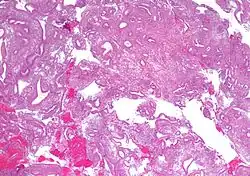

| Micrograph showing simple endometrial hyperplasia, where the gland-to-stroma ratio is preserved but the glands have an irregular shape and/or are dilated. Endometrial biopsy. H&E stain. | |

Like other hyperplastic disorders, endometrial hyperplasia initially represents a physiological response of endometrial tissue to the growth-promoting actions of estrogen. However, the gland-forming cells of a hyperplastic endometrium may also undergo changes over time which predispose them to cancerous transformation. Several histopathology subtypes of endometrial hyperplasia are recognisable to the pathologist, with different therapeutic and prognostic implications.[4]

- Endometrial hyperplasia (simple or complex) - Irregularity and cystic expansion of glands (simple) or crowding and budding of glands (complex) without worrisome changes in the appearance of individual gland cells. In one study, 1.6% of patients diagnosed with these abnormalities eventually developed endometrial cancer.[7]

- Atypical endometrial hyperplasia (simple or complex) - Simple or complex architectural changes, with worrisome (atypical) changes in gland cells, including cell stratification, tufting, loss of nuclear polarity, enlarged nuclei, and an increase in mitotic activity. These changes are similar to those seen in true cancer cells, but atypical hyperplasia does not show invasion into the connective tissues, the defining characteristic of cancer. The previously mentioned study found that 22% of patients with atypical hyperplasia eventually developed cancer.[7]